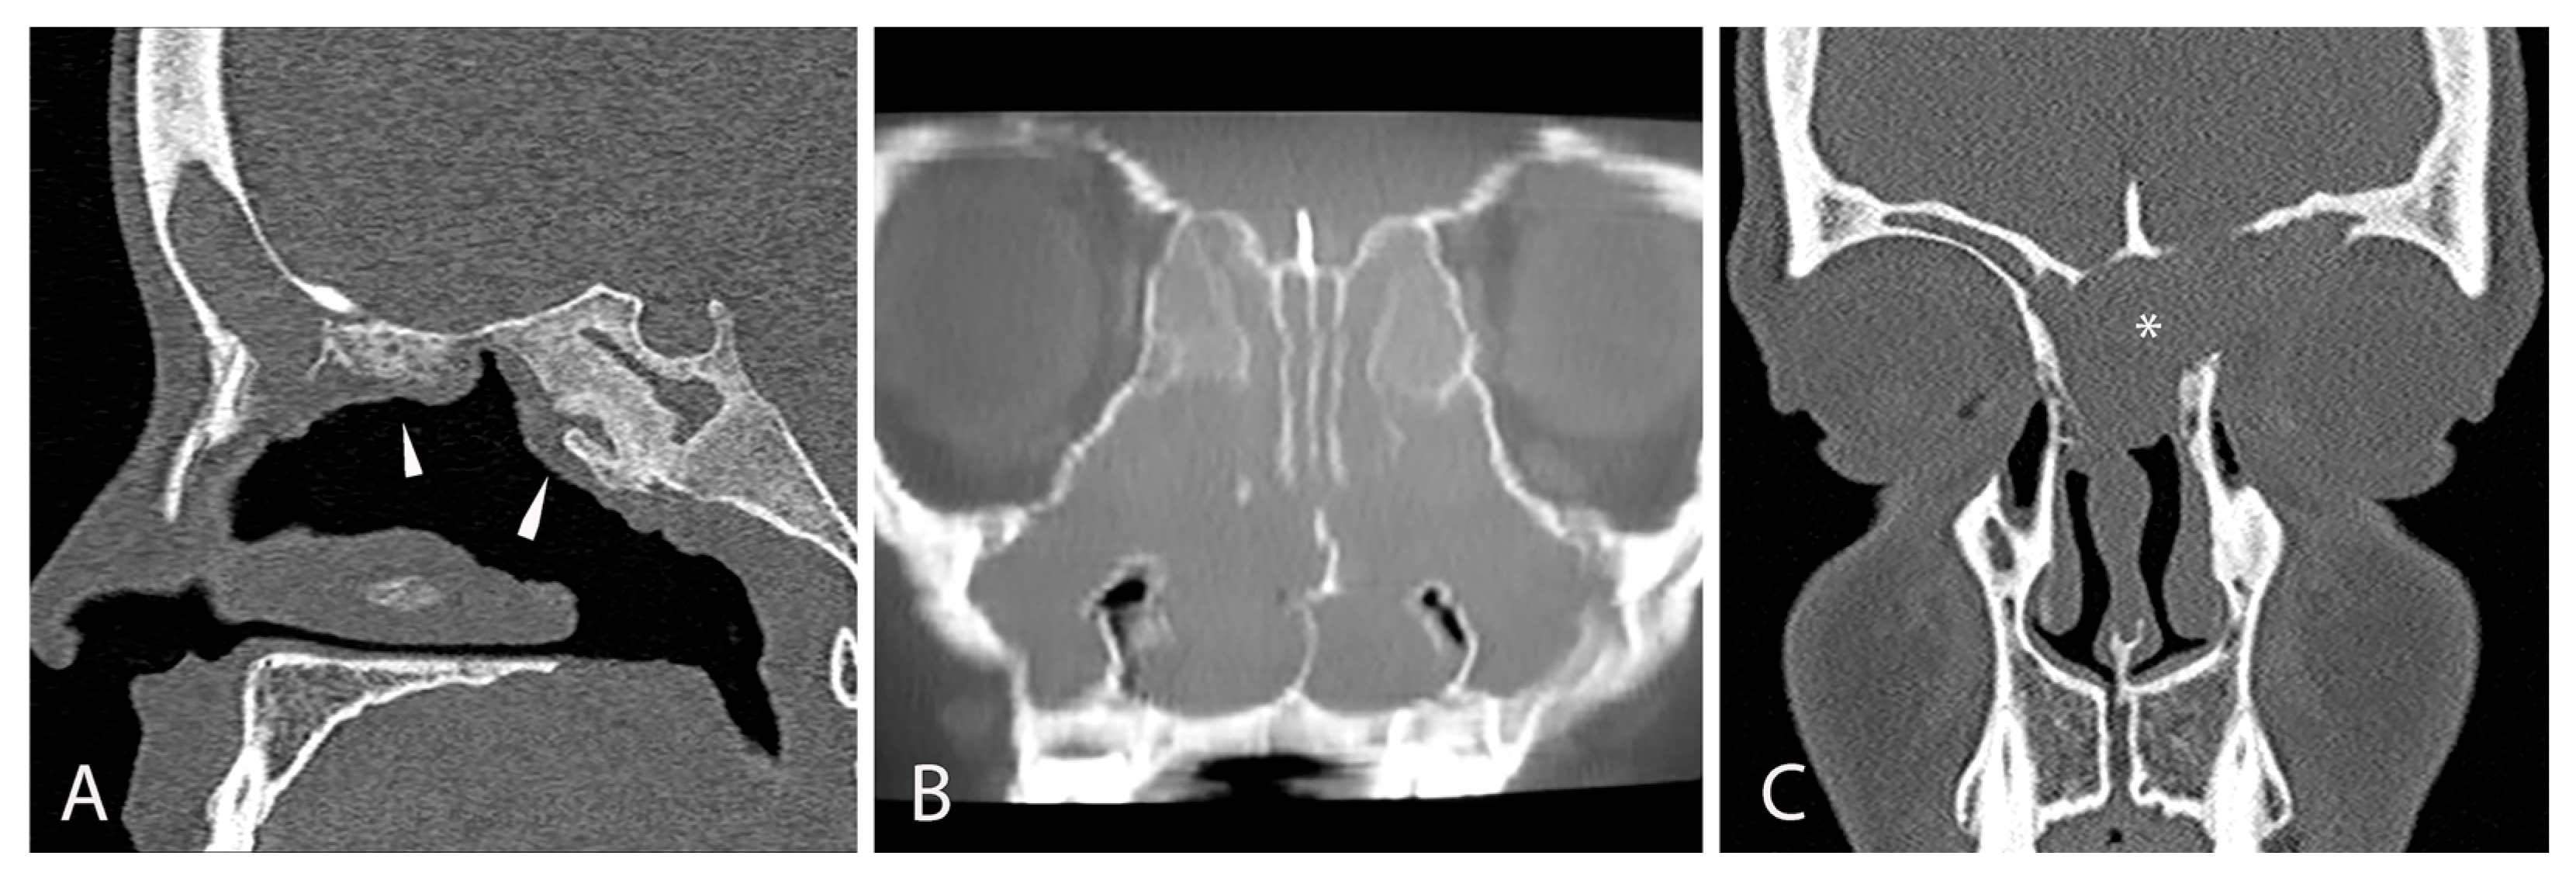

| Sinonasal Nasal obstruction (81.1%) (unilateral or bilateral) Rhinorrhea (50%) Hyposmia or anosmia (27%) Headache (50%) Facial pain Ocular Epiphora Exophtalmia Hyperemic conjunctive Others Mouth breathing Chronic cough Throat clearing Halitosis Activity intolerance Agitated or restless sleep Snoring Sleep apnea Failure to thrive | Nasal mucosa congestion, particularly with turbinates Prominent uncinate process Bulging of lateral wall (unilateral or bilateral) Nasal polyps (33–56.5%) Septal deformity Choanal stenosis Viscous and/or purulent nasal secretions Adenoid hypertrophy Cobblestoning of posterior pharynx | CT Opacification of the sinus (hourglass image) Mucocele Bulging or displacement of lateral nasal wall Demineralization of uncinate process Hypoplasia or aplasia of the paranasal sinuses Inverse relationship between the size of anterior and posterior ethmoid sinus Decreased pneumatization of the sinus MRI Mucosal swelling Mucopyoceles Polyps Maxillary sinus wall deformation Delay pneumatization | Bacteria Pseudomonas aeruginosa Staphylococcus aureus Haemophilus influenzae Streptococcus species Achromobacter xylosoxidans Fungi Candida albicans Aspergillus fumigatus Exserophilum species Penicillum species |